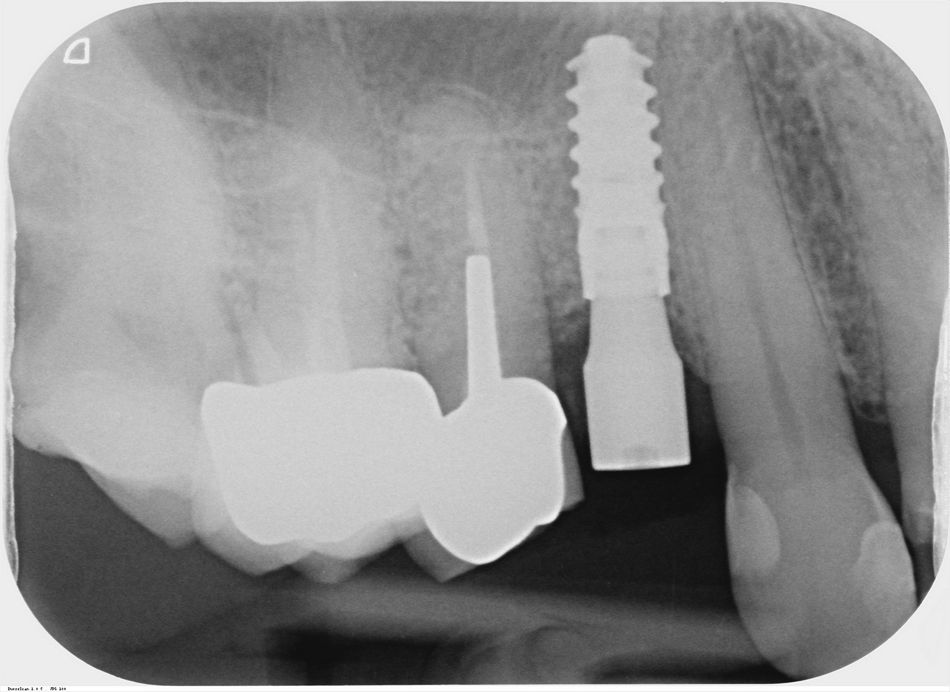

A Straumann® BLX 10 mm x 3.75 mm Roxolid® SLActive® implant was chosen because of its cut-condense-collect properties that redistribute native bone along the implant leading to high bone-to-implant contact. These features allow us to achieve ideal primary stability even in challenging clinical scenarios like this one (Figs. 6-8).

At the 6-month follow-up visit, a digital volume tomography (DVT) and a periapical X-ray were taken. An adequate bone volume, bone density, and 3D position were observed. (Figs. 13-15)